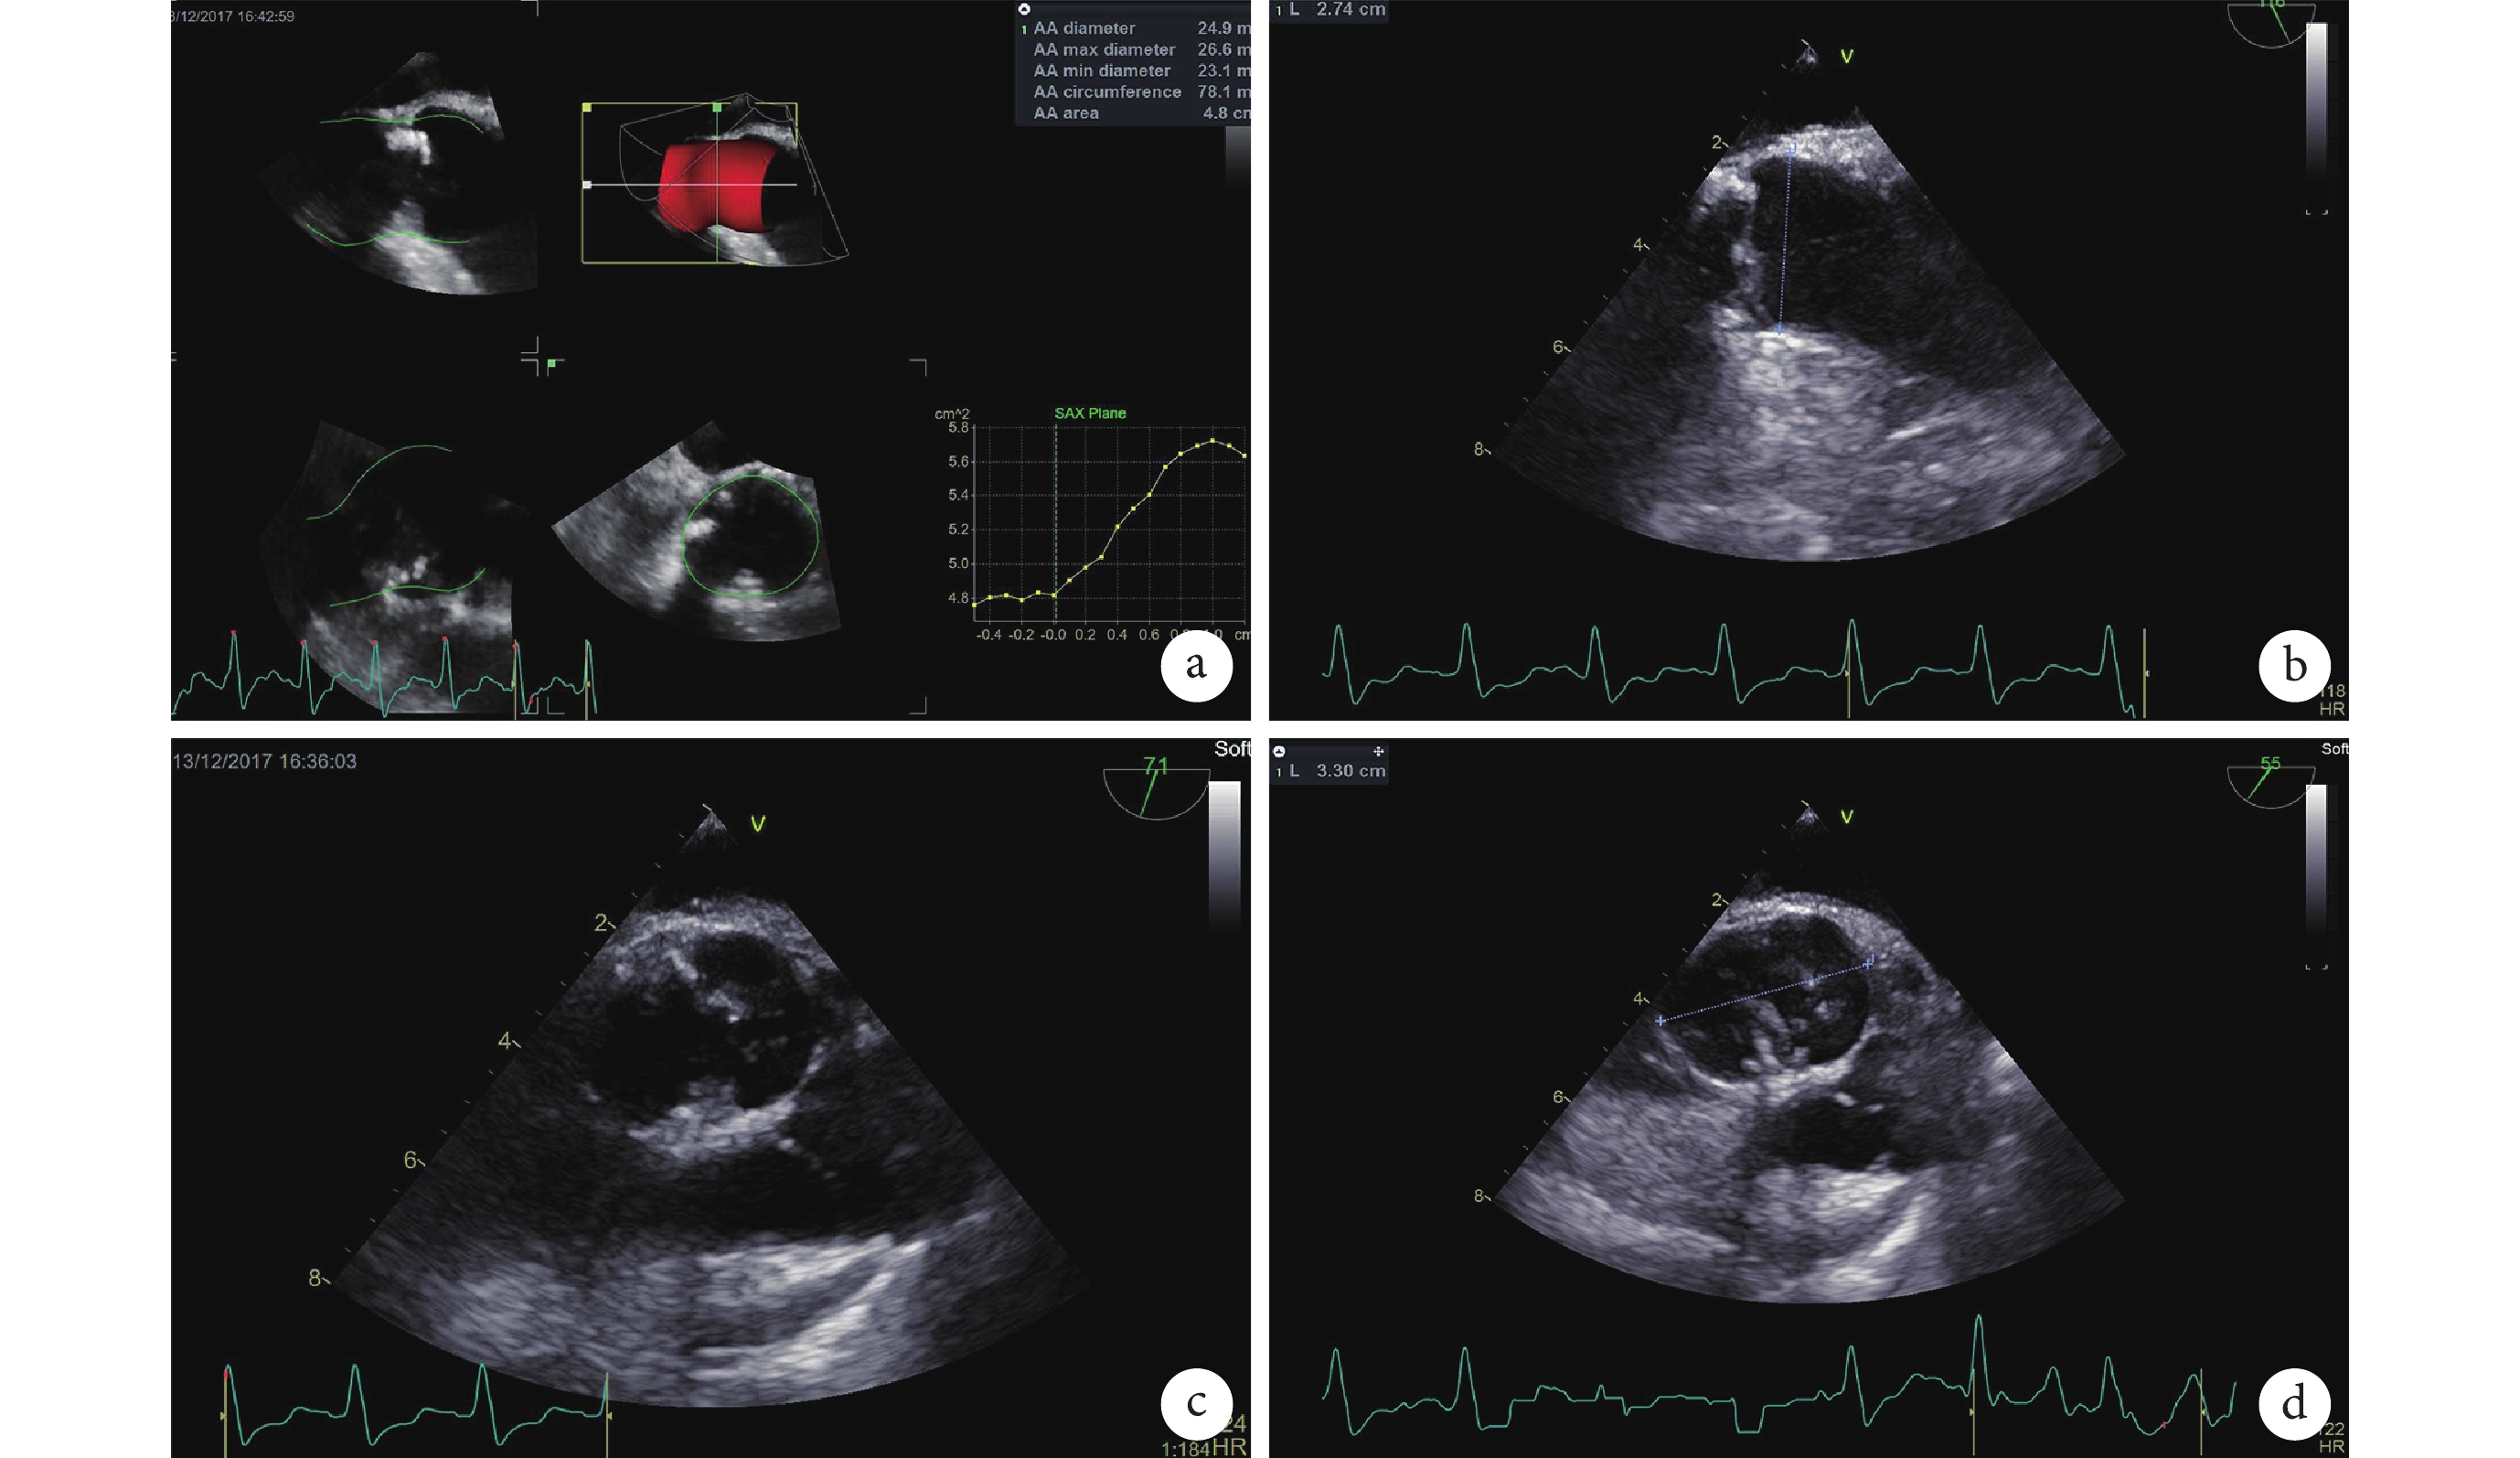

因患者血流動力學不穩定,故未行主動脈根部 CT 掃描。術前經食道超聲心動圖提示患者為“type 0”型二葉式主動脈瓣(圖1)。于 12 月 13 日全身麻醉下進行 TAVR,術中采用經食道超聲心動圖監測。術中以 TAV8 17 mm/22 mm 球囊(杭州啟明醫療器械有限公司)行預擴張后,在主動脈瓣病變處植入 26 mm Venus A 瓣膜(杭州啟明醫療器械有限公司,圖2)。術后經食道彩色多普勒超聲提示輕度瓣周漏,有創峰值壓差 2 mm Hg。

a. 三維主動脈瓣;b~d. 主動脈瓣切面圖。Type 0 型二葉式主動脈瓣,瓣環周長:78.1 mm,主動脈竇內徑:27.4 mm×33.0 mm